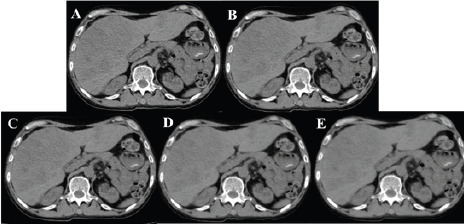

Objective: This study aimed to investigate the impact of Clear View dual-domain iterative reconstruction (IR) technology on the quality of low-dose abdominal CT images and to determine the optimal weight ratio to optimize image quality.

Methods: We studied 40 patients (28 males, 12 females, aged 19-69) undergoing low-dose abdominal CT scans (CTDI = 5.32 ± 0.89 mGy). The scanning parameters were set as follows: tube voltage of 120 kVp, tube current modulation based on Signal to Noise Ratio (SNR) at 0.5 mode (O-Dose automatic tube current modulation technology), pitch of 0.9, rotation time of 0.6 s/r, matrix size of 512 × 512, and collimation width of 16 × 1.25 mm. We applied Clear View IR with four weight ratios (20%, 40%, 60%, 80%) and filtered back projection (FBP). Conventional scanning uses with 120 kVp, 280 mAs, pitch of 0.9, rotation time of 0.6 s/r, matrix size of 512 × 512, and collimation width of 16 × 1.25 mm. Conventional dose abdominal CT scans (CTDI = 11.95 ± 0.00 mGy).CT values, standard deviations (SD), signal-to-noise ratio (SNR), and contrast-to-noise ratio (CNR) were measured for liver, spleen, pancreas, kidneys, and erector spinae muscles. Two deputy chief physicians blindly evaluated image quality on a 1-5 scale. Statistical analysis was done using SPSS 22.0 with P < 0.05 considered significant.

Results: Subjective evaluations revealed the highest diagnostic score with a 40% Clear View reconstruction weight ratio. Higher weight ratios significantly reduced subjective image noise, with the highest noise scores at 80%. Moreover, compared to FBP, especially Clear View reconstruction weight ratios of 20% to 60%, significantly improved the image quality of abdominal solid organs, reducing image artifacts and improving diagnostic acceptability (P < 0.05). Objective evaluation showed that with increasing Clear View reconstruction weight ratios, image noise SD values decreased, while SNR and CNR values increased, and the differences in SD, SNR, and CNR for different reconstruction weight ratios of abdominal solid organs were statistically significant (P < 0.05).

Conclusion: Compared to FBP algorithm, Clear View demonstrates greater potential in low-dose abdominal CT, effectively reducing image noise and artifacts while maintaining image clarity. Based on combined subjective and objective evaluations, a 40% Clear View reconstruction weight ratio provides optimal image quality for abdominal solid organs.